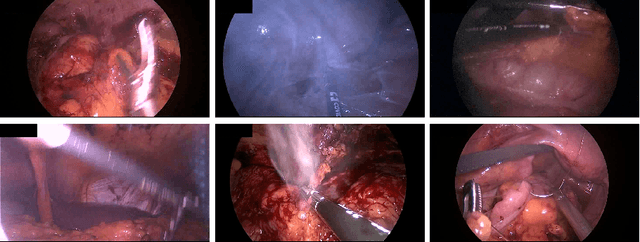

Abstract:Precisely locating and segmenting medical instruments in images of minimally invasive surgeries, medical instrument segmentation, is an essential first step for several tasks in medical image processing. However, image degradations, small instruments, and the generalization between different surgery types make medical instrument segmentation challenging. To cope with these challenges, we adapt the object proposal generation system AttentionMask and propose a dedicated post-processing to select promising proposals. The results on the ROBUST-MIS Challenge 2019 show that our adapted AttentionMask system is a strong foundation for generating state-of-the-art performance. Our evaluation in an object proposal generation framework shows that our adapted AttentionMask system is robust to image degradations, generalizes well to unseen types of surgeries, and copes well with small instruments.